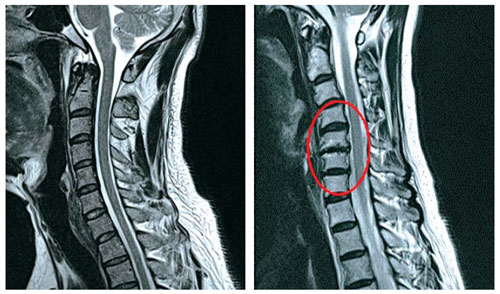

목 디스크는 목의 디스크(경추 디스크)에서 출현하는 질환으로, 경추 디스크 사이의 연골판이 터져 디스크 내부 물질이 경추 신경을 자극해 통증이나 저림증 등의 증상을 유발 해요. 목 디스크는 일상생활에서의 안 좋은 자세나 많은 운동, 부상 등이 이유가 되는 것이 될 수 있기도하고, 시간이 지날수록 발생 확률이 높아져요. 목 디스크의 증상으로는 목 부위의 통증, 팔의 저림, 근육 약화 등이 있으며, 증상이 난폭한 경우 수술 등의 치료가 필요할 수 있어요. 그리하나 대개의 경우 치료 없이도 시간이 지나면 증상이 호전되는 경우가 대부분입니다.

척수라는 중추 신경은 목뼈를 통과해 목 아래 감각과 운동 신경에 영향을 끼치기 때문에 목 디스크 증상들이 나타나면 신속하고 빠른 대처가 필요해요. 목디스크 치료형식으로 주로 초기 스탭에는 물리치료나 약물을 통해 대개의 환자들이 호전돼요. 그렇지 않다고 하면 신경 성형술과 차단술이라고 부르는 뼈주사 목디스크 치료방법을 이용하는데, 이 치료방법은 통증이 있는 신경 부위에 약물을 삽입하는 것입니다.